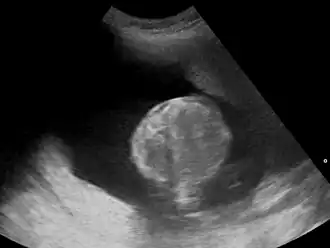

Многоводие (синоним греч. полигидрамнион) — патологическое состояние, при котором наблюдается избыток околоплодных вод в амниотической полости. По статистике, наблюдается у 1 % беременных женщин[3][4][5]. Существует два типа многоводия: